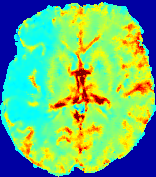

LesionRefer to captionRefer to captionRefer to captionRefer to captionRefer to captionRefer to caption𝐕rgbsubscript𝐕𝑟𝑔𝑏{\bf{V}}_{rgb}Refer to captionRefer to captionRefer to captionRefer to captionRefer to captionRefer to caption𝐕2subscriptnorm𝐕2{\|\bf{V}}\|_{2}Refer to captionRefer to captionRefer to captionRefer to captionRefer to captionRefer to captionRefer to caption3.53.53.52.82.82.82.12.12.11.41.41.40.70.70.70.00.00.0(mm/s)𝑚𝑚𝑠(mm/s)D𝐷DRefer to captionRefer to captionRefer to captionRefer to captionRefer to captionRefer to captionRefer to caption0.0200.0200.0200.0160.0160.0160.0120.0120.0120.0080.0080.0080.0040.0040.0040.0000.0000.000(mm2/s)𝑚superscript𝑚2𝑠(mm^{2}/s)Slice #1Slice #2Slice #3Slice #4Slice #5Slice #6

Figure 4: PIANO feature maps for another patient in the ISLES 2017 training set, where the lesion is located in the right hemisphere. Top row: segmented stroke lesion region (white) on different slices. The corresponding slices for the PIANO feature maps are shown in the following rows.

For a better insight into an estimated velocity field 𝐕𝐕{\bf{V}} and diffusion field 𝐃𝐃{\bf{D}}, we compute the following maps: (1) 𝐕rgbsubscript𝐕𝑟𝑔𝑏{\bf{V}}_{rgb}: Color-coded orientation map of 𝐕=(Vx,Vy,Vz)T𝐕superscriptsuperscript𝑉𝑥superscript𝑉𝑦superscript𝑉𝑧𝑇{\bf{V}}=(V^{x},V^{y},V^{z})^{T}, obtained by normalizing 𝐕𝐕{\bf{V}} to unit length and mapping its 3 components to red, green, blue respectively; (2) 𝐕2subscriptnorm𝐕2\|{\bf{V}}\|_{2}: 222 norm of 𝐕𝐕{\bf{V}}; (3) D𝐷D: scalar field in Eq. 5.

Fig. 3 and Fig. 4 show the PIANO feature maps estimated from two ISLES 2017 patients: all are highly consistent with the lesion in both cases. Details of the blood flow trajectories are revealed in 𝐕rgbsubscript𝐕𝑟𝑔𝑏{\bf{V}}_{rgb} by the ridged patterns and the sharp changes of colors in the unaffected (right) hemisphere, while the flat patterns appearing within the lesion provide little directional information about the velocity and indicate low velocity magnitudes. Velocity magnitudes are more directly visualized via 𝐕2subscriptnorm𝐕2\|{\bf{V}}\|_{2}, from which one can easily locate the lesion where 𝐕2subscriptnorm𝐕2\|{\bf{V}}\|_{2} is low. D𝐷D also indicates lower diffusion values in the lesion, though with less contrast potentially due to the fact that it captures the accumulated effect of CA diffusion at the voxel-level.